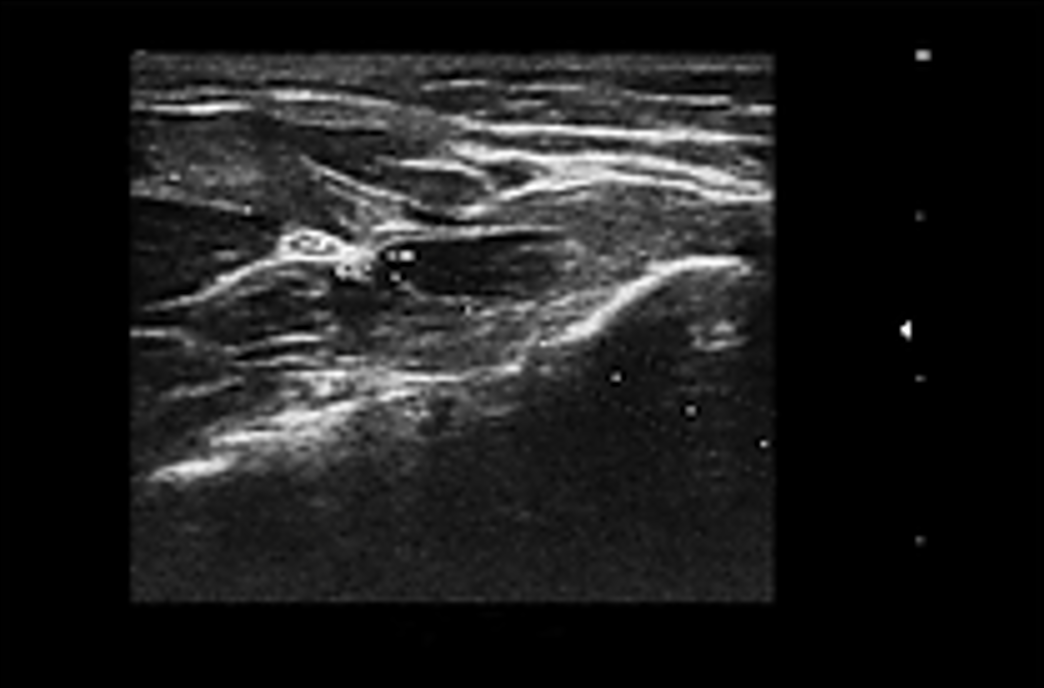

eNeedle การเสริมประสิทธิภาพสำหรับการเจาะชิ้นเนื้อด้วยอัลตราซาวด์ เทคโนโลยี eNeedle ช่วยเพิ่มความคมชัดในการมองเห็นเข็มจากสภาพแวดล้อมรอบข้าง แสดงเส้นทางการแทรกเข็มสำหรับการเจาะชิ้นเนื้อ และช่วยให้ผู้ปฏิบัติงานสามารถทำการผ่าตัดได้อย่างมีประสิทธิภาพ |

- หัวตรวจอาร์เรย์ไมโครคอนเวกซ์ความถี่สูงเหมาะสำหรับการใช้งานทั่วร่างกายสัตว์เลี้ยง

- หัวตรวจอาร์เรย์เส้นตรงขนาดเล็กความถี่สูงถูกออกแบบมาเพื่อสัตว์เลี้ยงชนิดพิเศษ (exotic pets) ซึ่งช่วยบาลานซ์การแก้ไขความละเอียดและการซึมผ่านได้ดียิ่งขึ้น